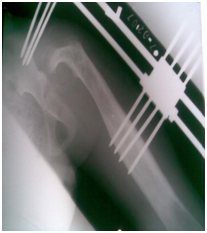

Figure 2 Across hip Naseer Awais External Fixator applied for control distraction of proximally migrated femoral head, 2mm per day.

Figure 3&4 Showing distraction started process is going on 2mm per day, to avoid Neuro-vascular injury.

Figure 5 showing Radiograph 3 weeks after distraction is on progress by applying NA Ex Fix.